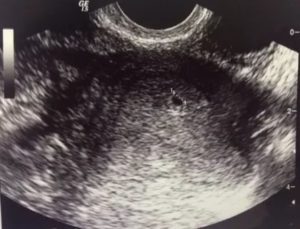

Вагинальное УЗИ зачастую выполняется на ранних сроках беременности. С начала второго триместра такое исследование – не распространенная практика, однако имеет ряд показаний в отдельных случаях. С его помощью можно оценить состояние шейки матки, определить предлежание детского места и т.д.

Для этого делают ультразвуковое исследование. После УЗИ при беременности бывают коричневые выделения. Нормой считаются скудная мазня, небольшой тонус, слабые боли внизу живота.

Этот вид исследования на ранних сроках беременности дает более точную картину нахождения плода в матке и состояния половых органов женщины. Процедура проводится быстро. Врач назначает ее по показаниям.

Находясь в утробе, ребенок защищен околоплодными водами и шейкой матки от внешнего воздействия. Поэтому кровь после трансвагинального УЗИ в большинстве случаев просто совпадение.

Но если после 12 недели проводится ультразвуковое наружное исследование, то до этого срока делается вагинальное УЗИ.

Во время него используется специальное устройство в виде трубки оснащенной камерой, которая подается во влагалище женщины и выводит изображение на монитор компьютера.

Такое УЗИ считается наиболее информативным, так как оно позволяет получить полную картину о состоянии репродуктивных органов и о протекании беременности.